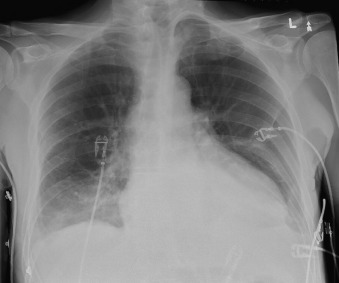

A pericardial effusion ( Figs. 16-1 to 16-15 ) is often suggested on the frontal chest radiograph by a smoothly distended, “flasklike” CPS. More than 500 mL of fluid must be present before the change in the CPS is fairly obvious. A flasklike appearance may be caused by myocardial disease as well; scrutiny of the hilar vessels may distinguish the two. In the presence of pericardial effusion, the hilar vessels are covered (the pericardium runs up onto them and obscures them). In the presence of myocardial disease, the hilar vessels are unusually prominent as they are distended under higher than usual pressure.

In a minority of patients with pericardial effusion, on the lateral radiograph, a stripe of radiolucent epicardial fat, a “fat line,” may be visible anteriorly, suggesting fluid in the pericardial space. A stripe greater than 2 mm is abnormal. This “pericardial stripe sign” is more easily seen in adults than children (more fat!).

A prominent azygous vein, superior vena cava, or inferior vena cava suggests cardiac tamponade.

Echocardiography is the diagnostic test of choice for the evaluation of pericardial effusions. Pericardial tamponade remains a clinical diagnosis, strengthened by supportive echocardiographic findings.